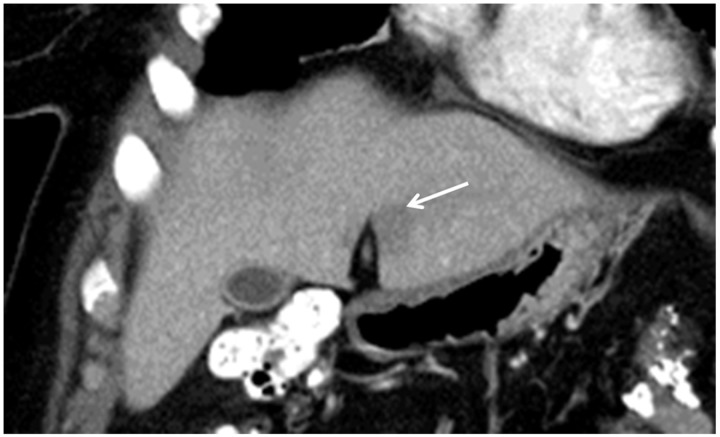

Figure 2.

Focal hepatic steatosis adjacent to the falciform ligament in a patient with breast cancer. Coronal reformatted contrast-enhanced CT scan shows a hypodense “lesion” (arrow) in segment III. Its location strongly suggests that it represents focal fat.

During the HAP, a hypovascular region that can simulate a metastasis is often seen in segment IV (Fig. 3) adjacent to the falciform ligament which on PVP or delayed images becomes isodense with the liver. This may result from the aberrant venous blood flow or be attributable to this region being is a watershed area of hepatic arterial and portal venous blood flow[32].

Figure 3.

Transient hepatic attenuation difference (THAD) adjacent to the falciform ligament in a patient with colon cancer. Contrast-enhanced CT shows a focal hypodense region in segment IV that became isodense in later phases. This appearance and location are classic for a THAD.